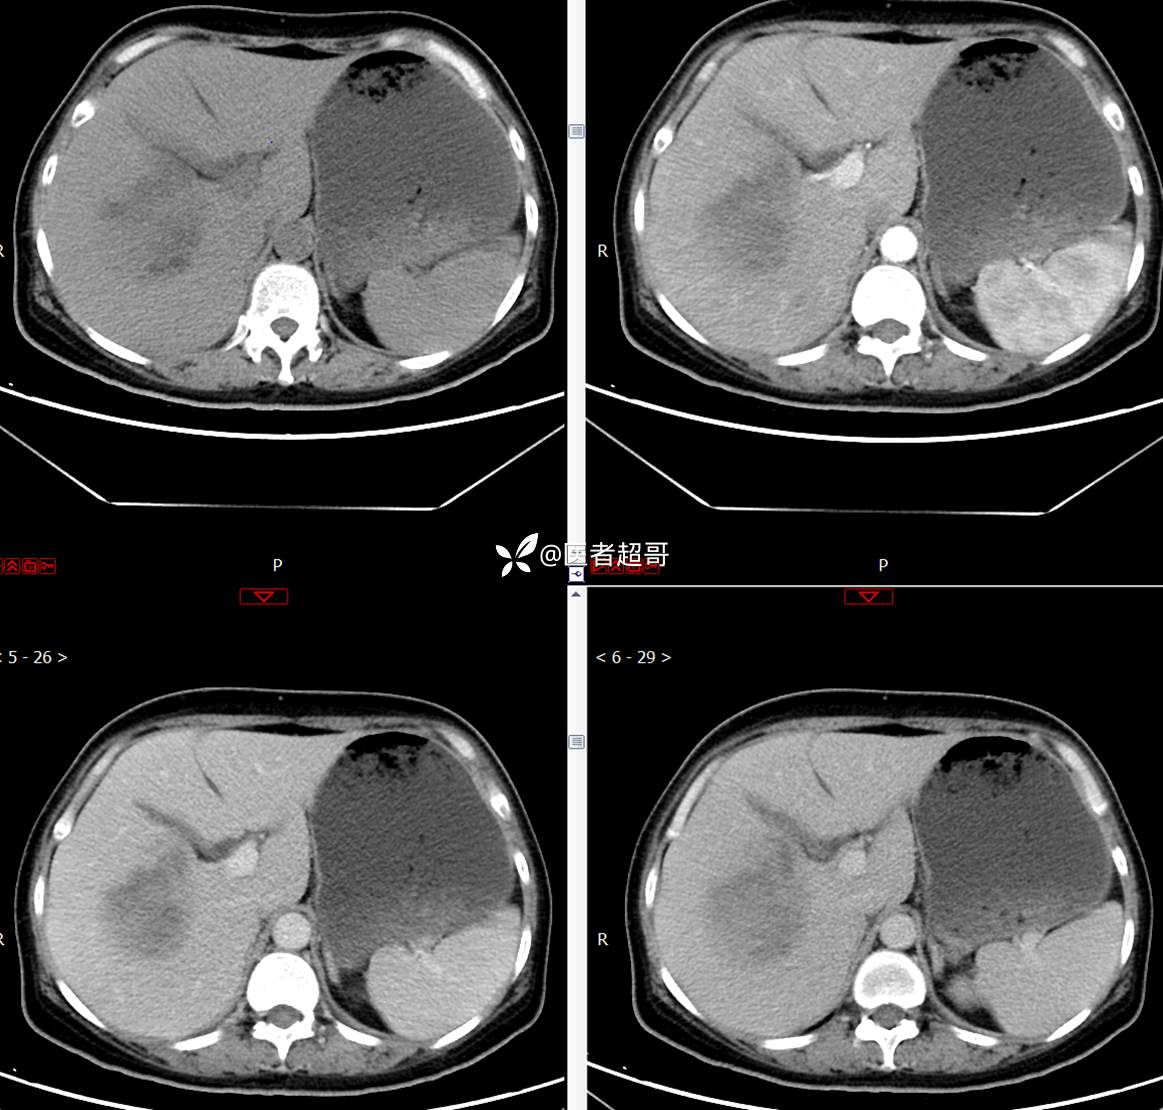

现病史:患者1周余前发现右上腹有一半球形巨大肿物,约18cm*15cm大小,既往贫血病史3年余,诉乏力,易疲劳,偶有头晕,活动后心悸,无腹痛、腹胀,无恶心、呕吐,无尿频、尿急、尿痛,无排尿困难,患者为求进一步治疗,来我院消化内科就诊,门诊行肝.胆.胰.脾.肾彩超示:右肾上部囊实性占位,范围约18.0cm×11.7cm×16.4cm,边界清,形态规则,建议进一步检查,腹膜后实性结节。我科遂以“肾肿物”收治入院,患者自发病以来,神志清、精神可,睡眠、饮食可,二便正常,体重、体力略有下降。